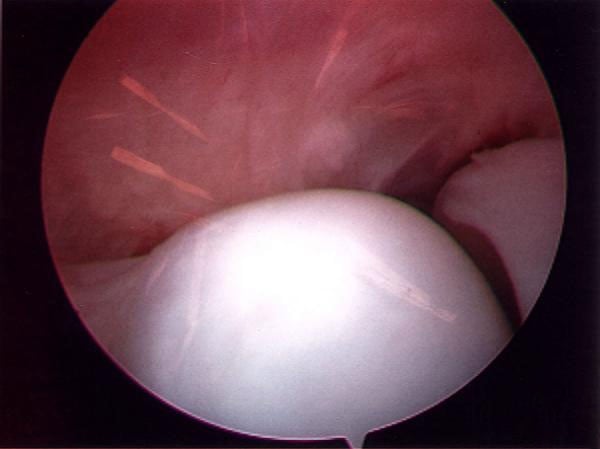

As in other joints, arthroscopy of the elbow involves the use of fiberoptics and a tiny camera that is inserted through small incisions or portals. Magnified pictures from the camera are projected onto a television monitor in the operating suite. When the procedure is employed to treat an injured or diseased joint, the orthopedic surgeon inserts miniaturized surgical instruments through an additional portal.

Image of the elbow joint obtained through arthroscopy.